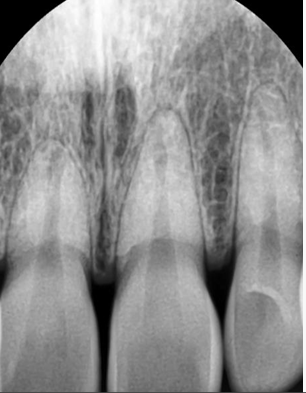

앞니치근사진